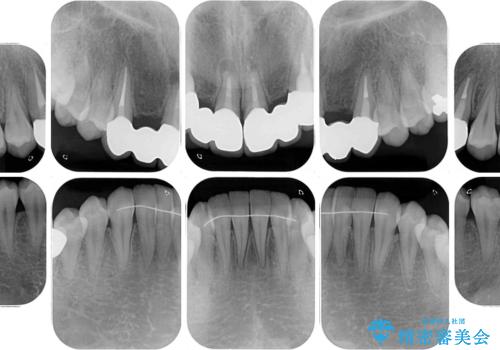

- 審美的ではない上の前歯とデコボコの下の前歯、歯茎が腫れている奥歯を気にして来院された患者様です。

根管治療の必要な歯がいくつかあるため、まずは根管治療を行い、その後インビザラインにて矯正治療を行うこととしました。

矯正治療後に前歯をセラミックブリッジに、奥の銀歯はセラミックインレーやPGAインレー(ゴールドインレー)にて補綴・修復治療を行うこととしました。